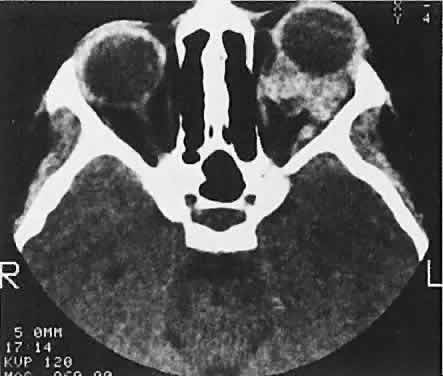

Sporadic North American cases have a less-definitive viral association. These patients differ clinically in their age of presentation (mean, 11 years) and in the usual site of tumor origin (intra-abdominal lymphoid tissue).40,41 Involvement of the facial bones and orbit is less common in the North American cases, but invasion of the orbit from the sinuses may occur42,43 (Fig. 4).

Fig. 4. Burkitt's lymphoma involving the posterior ethmoids, skull base, and both orbital apices in a 5-year-old boy.